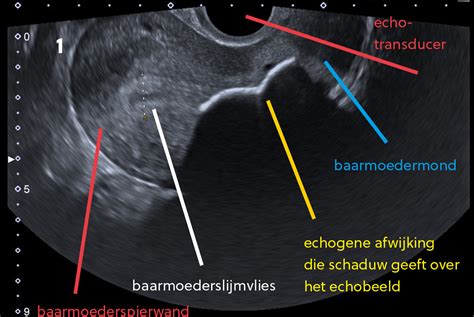

8K - Fotorealistische Echo

Een bijzondere nieuwe aanwinst bij De Luiermand is de mogelijkheid tot een 8K - fotorealistische echo. Deze geavanceerde echotechnologie biedt een indrukwekkende, gedetailleerde impressie van de ongeboren baby, waardoor ouders een nog levendiger beeld krijgen van hun kindje voordat het geboren is. Het is een emotioneel moment dat de band met de baby versterkt.